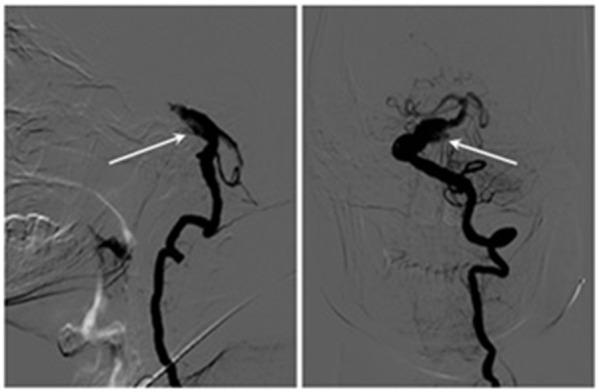

Trigeminal neuralgia secondary to vertebrobasilar dolichoectasia and basilar artery dissection is rare. The authors report the case of a 72-year-old man with a 5-year history of right electrical facial pain identical with trigeminal neuralgia. Finally, magnetic resonance imaging and digital subtraction angiography revealed basilar artery dissection and vertebrobasilar dolichoectasia. The patient underwent partial basilar dissecting aneurysm embolization. The facial pain was relieved immediately after the operation and disappeared completely 6 months later. Three years after surgery, the patient had experienced no recurrence of the right facial pain.

继发于椎基底动脉延长扩张症和基底动脉夹层的三叉神经痛很罕见。作者报告了一例72岁男性患者,其右侧面部电击样疼痛病史5年,与三叉神经痛症状相同。最终,磁共振成像和数字减影血管造影显示基底动脉夹层和椎基底动脉延长扩张症。该患者接受了部分基底动脉夹层动脉瘤栓塞术。术后面部疼痛立即缓解,6个月后完全消失。术后三年,患者右侧面部疼痛未复发。